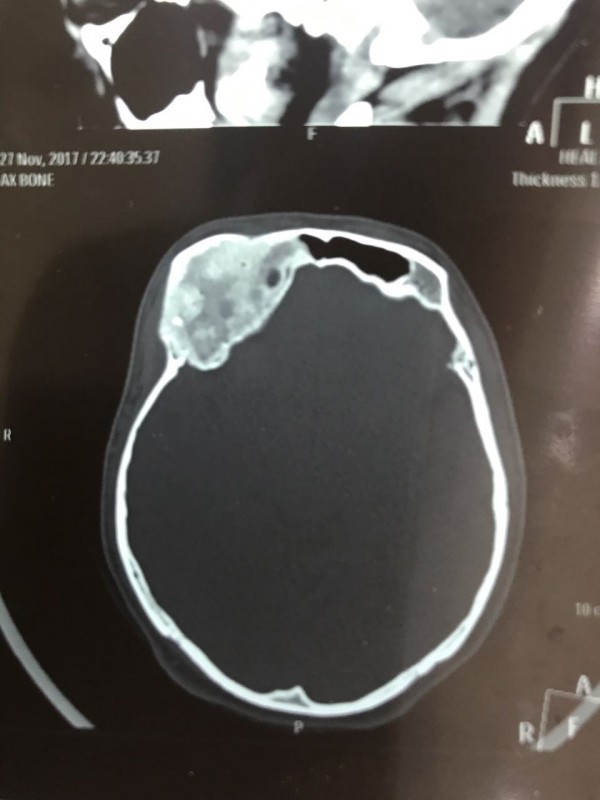

"Компьютерная томография показала, что костная опухоль поражала лобную кость и "крышу" орбиты глаза, которая, в свою очередь, сдавливала глазное яблоко. Чтобы убрать опухоль, потребовалось немало времени. Наша задача была сохранить глазное яблоко, зрительный нерв и сосуды. Если неправильно провести операцию и неправильно закрыть дефект, то в последующем это может привести к эстетической неполноте и асимметрии лица. Уникальность еще и в том, что в операции применялась 3D-стереолитография, которая делается только в Алматы", - рассказал он.

Снимок сделан до операции. Фото предоставлено Константином Ли